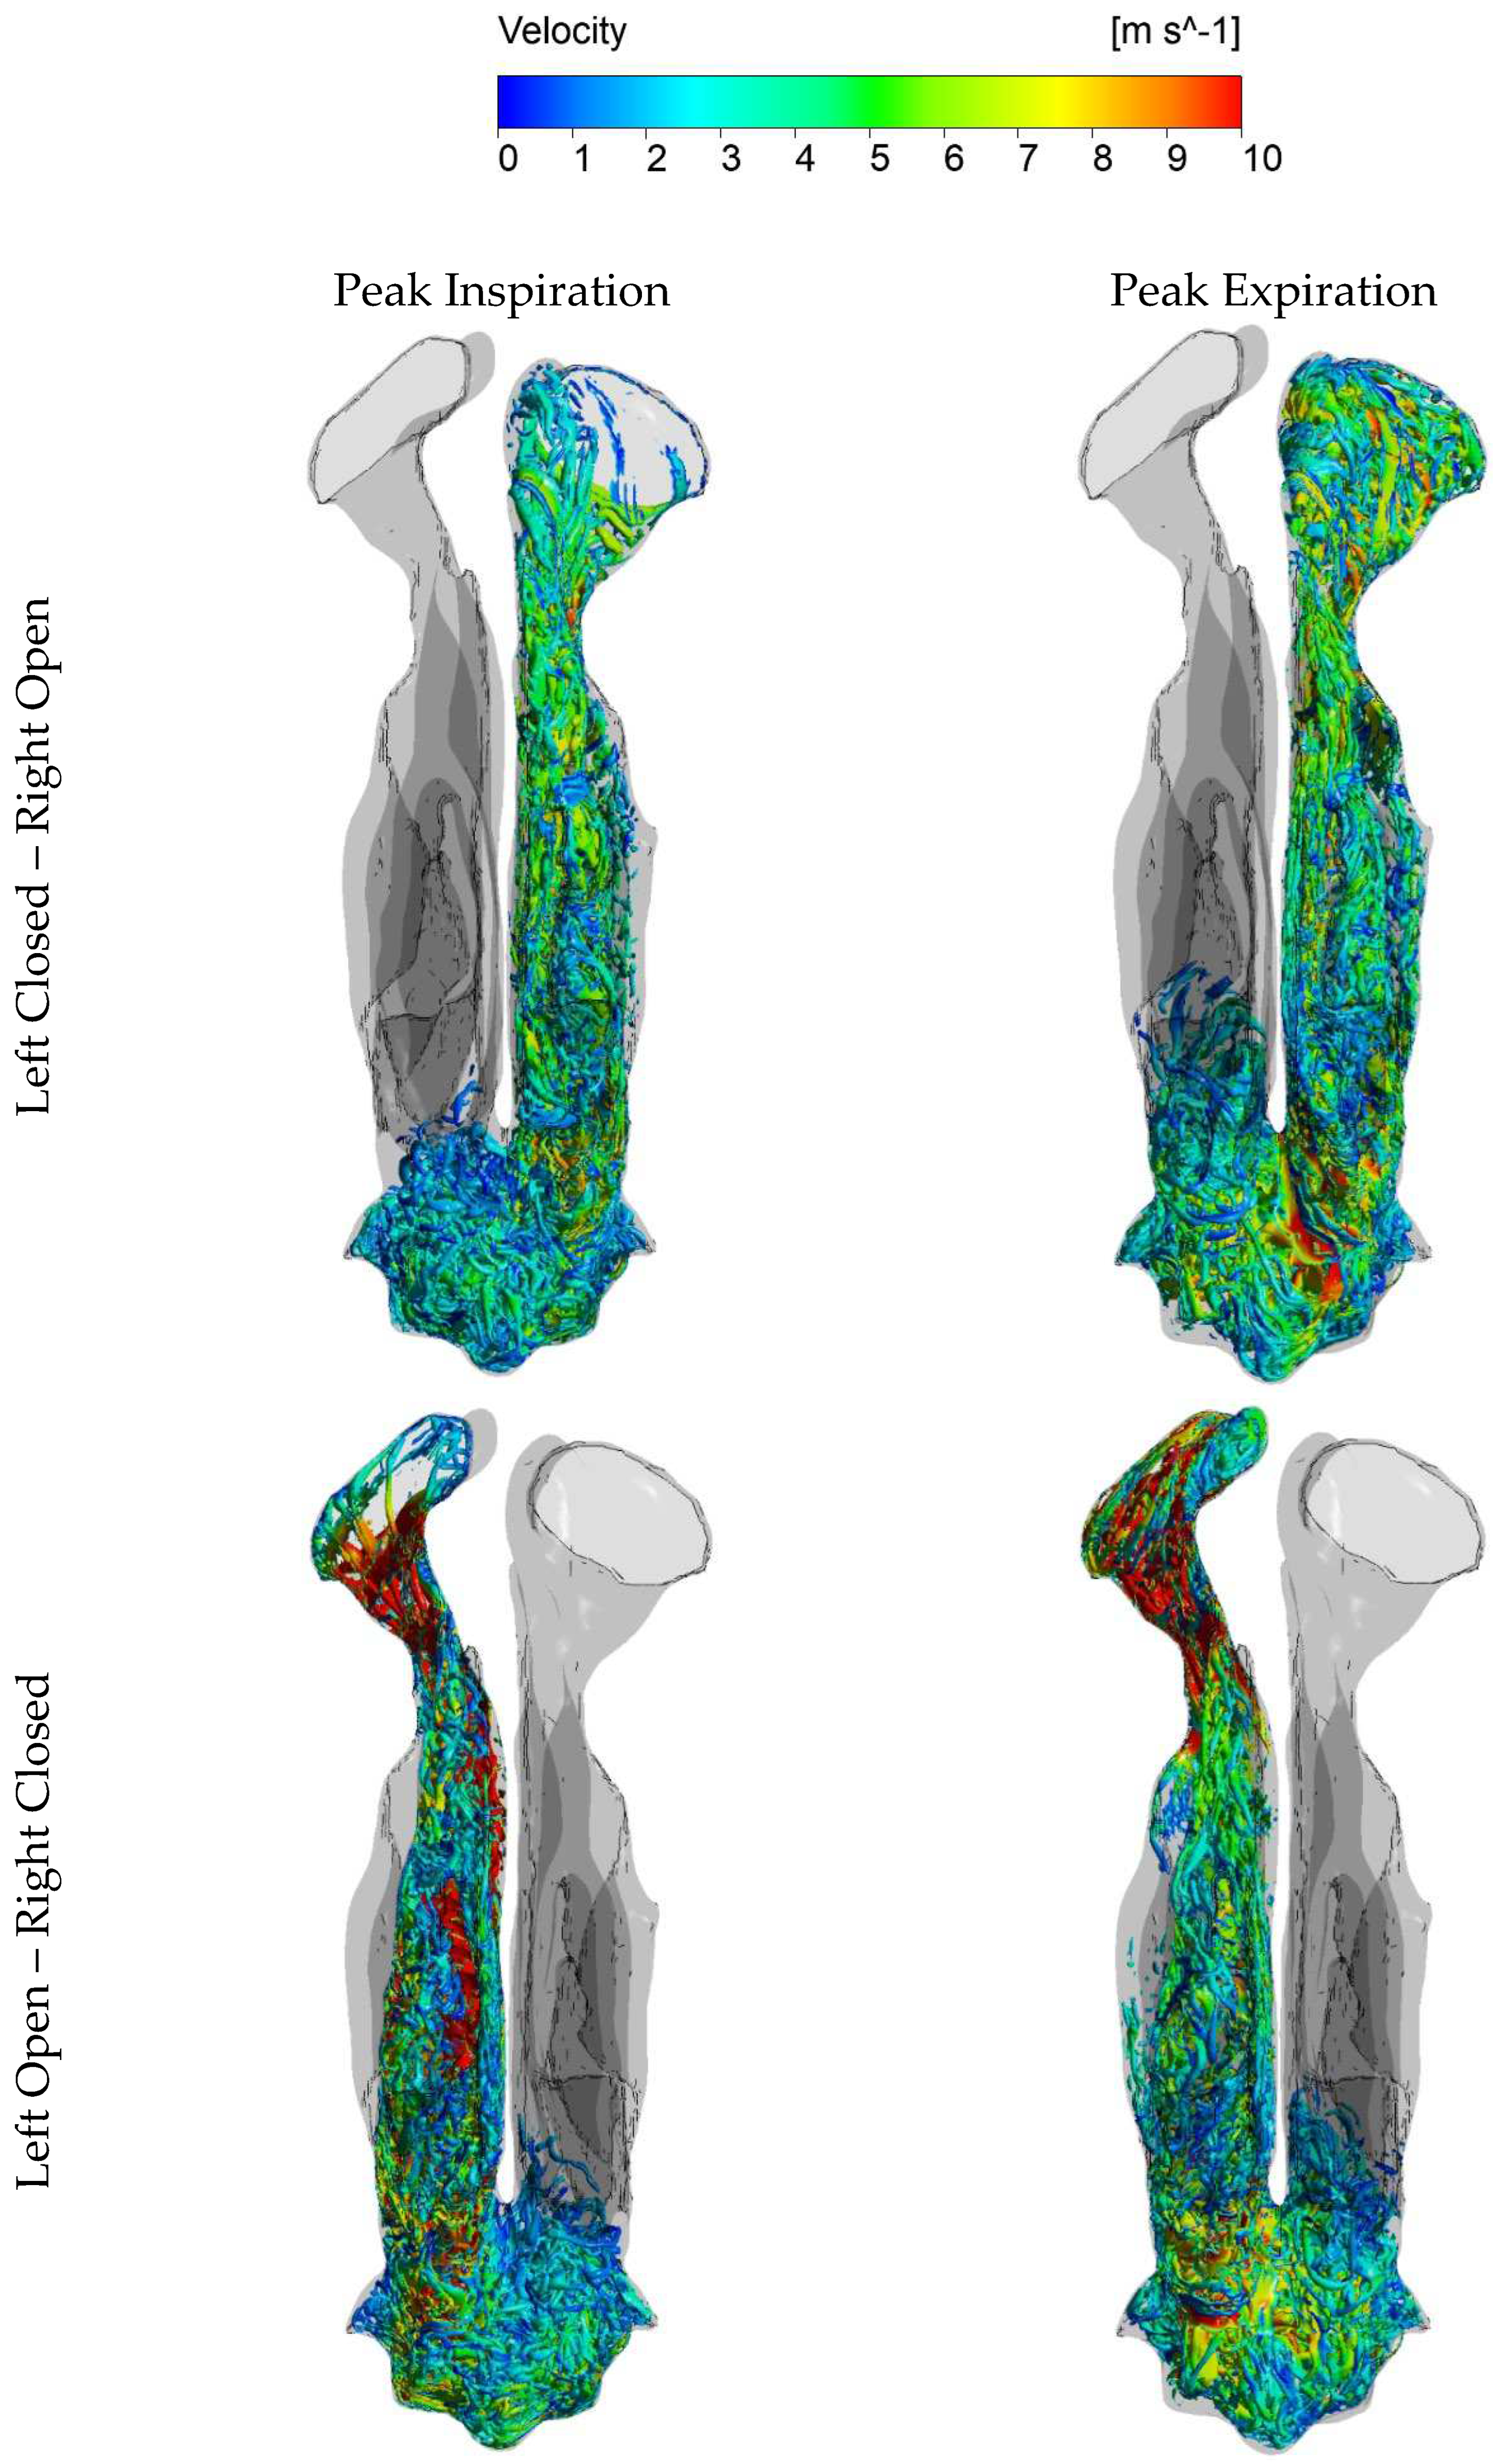

III.2.3 Flow velocity fields.

- Modeling the entire airway, including the lungs and alveoli, is impractical in nasal airflow studies. Therefore, the airway is typically truncated somewhere in the laryngopharyngeal tract. The location of this truncation has traditionally been based on available computational resources and the specific phenomena of interest. Although the location of truncation may be less critical during inhalation, more attention may be warranted during exhalation. Wu et al. [181] demonstrated in a physical experiment, that the flow in the pharynx is laminar during normal breathing, but Bradshaw et al. [159] highlighted the importance of including a realistic pharyngeal tract to achieve accurate flow conditions in the nasopharynx during exhalation. The pharyngeal tract is a complex, soft-tissue-enclosed flow channel susceptible to head and neck movements, swallowing, tongue movement, and compliance with over/under pressure due to breathing. The exhalatory flow pattern entering the nasopharynx is likely to be affected by this. The level of realism required in the pharyngeal tract to attain acceptable inflow to the nasopharynx is still unresolved.